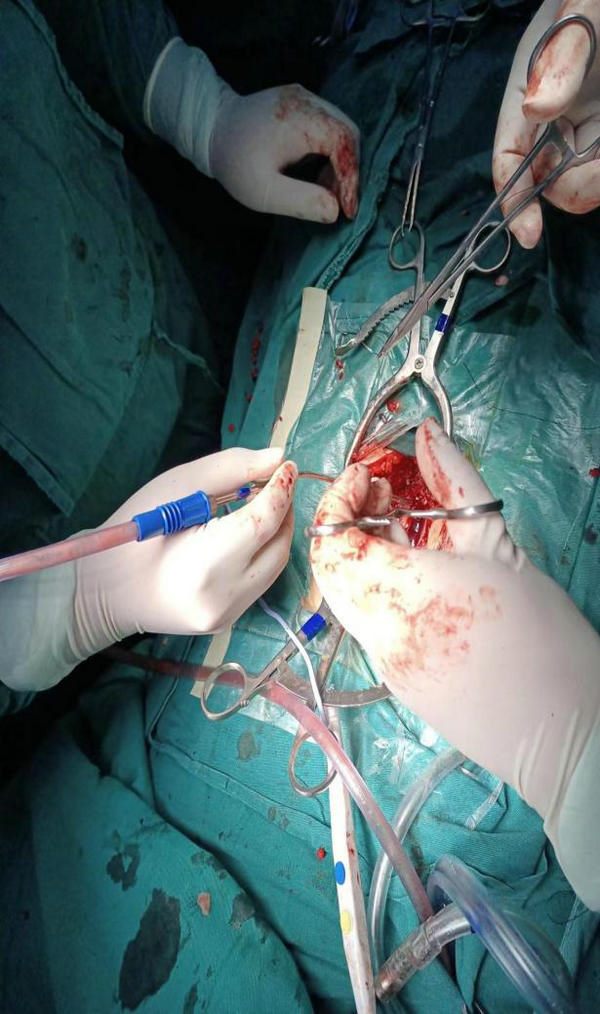

寿记新科主任、王建业副主任医师、高海东主治医师等科室医护人员紧急讨论病情后,制定了详细的手术救治方案后,在医院麻醉科、神经电生理等科室协作下紧急为患者进行了神经显微镜下“脊髓内肿瘤切除术”。经过医护共同努力,术后患者双下肢运动功能即刻恢复,可自主抬起双腿,经过术后治疗和康复锻炼,患者已逐渐恢复排便排尿功能,术后病理证实,占位为室管膜瘤合并肿瘤卒中,后续进一步治疗也在进行中,患者及家属对郑州大学五附院神经外科医护团队高度称赞,并送来锦旗对医护人员表示感谢。